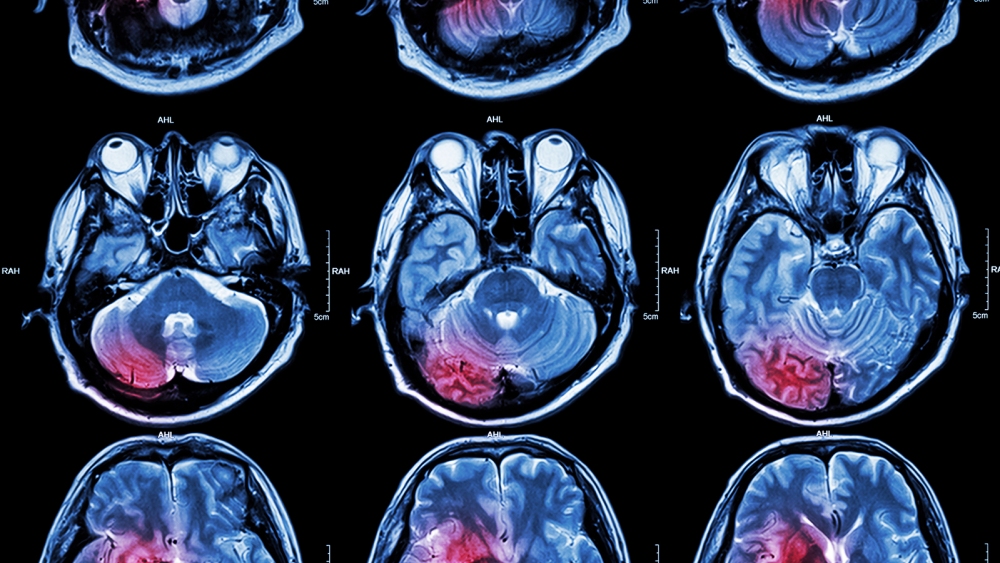

Dementia frequently occurs after a stroke, causing memory, gait, and focus problems. It is thought to be a side effect of the body’s natural immune response to dead brain tissue left behind after a stroke.

The problem: When blood vessels in the brain become clogged or constricted, they can cut off oxygen and nutrients to the brain and destroy brain cells. This is the root cause of ischemic strokes.

However, after a stroke, the leftover dead tissue triggers an inflammatory response, where immune cells flood the site of injury to clean up any dead or damaged cells so healing can progress.

But prolonged inflammation can also harm good tissue, which can lead to post-stroke dementia.

Brain cells are also packed with cholesterol, which is difficult for immune cells to eliminate. So inflammation caused by a stroke might linger for months, spreading to healthy areas of the brain and killing more brain cells.